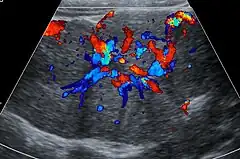

Unenhanced CT or MRI usually does not show the difference in intensity between the focal nodular hyperplasia and surrounding liver except when there is marked liver steatosis that reduces the attenuation of the liver, causing focal nodular hyperplasiato be hyperattenuating when compared with the surrounding liver. In the arterial phase CT or MRI, there is a strong enhancement not followed by washout. The lesion presents a slight hyperintensity or isodensity on portal venous phase or delayed phase images. There is also a presence of a central scar and absence of a capsule for the focal nodular hyperplasia.[7]

The prevalence of focal nodular hyperplasia in individuals undergoing evaluation with an ultrasound of the abdomen is 0.03%.[9] About 20% of focal nodular hyperplasia lesions are associated with hepatic hemangiomas.[9]